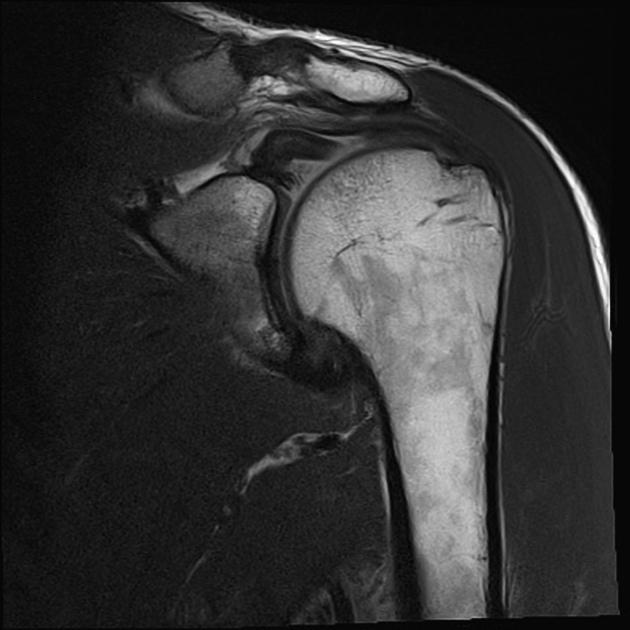

- MRI: Magnetic resonance imaging (MRI) offers detailed images of the soft tissues, including the shoulder and biceps tendons. It helps in assessing the extent of the injury and determining the best course of treatment.